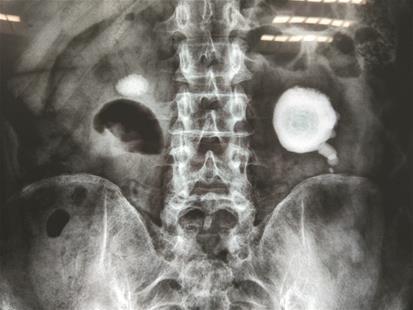

原標題:熬夜加班喝水少 泡完的茶葉嚼著吃 圖文:恩施男子左腎長出“荷包蛋”結石

加班頻繁,喜歡喝濃茶,還有“吃茶葉”的喜好,發現結石后還一拖再拖,結果雙腎均被結石“霸占”。近日,恩施的一位先生在武漢京都結石醫院順利完成雙鏡聯合微創保腎取石手術,將撐滿左腎的“荷包蛋”結石及右腎兩公分結石全部取出。

“腎結石長得像荷包蛋,這以后雞蛋是吃不下去了。”在武漢京都結石醫院病房內,該先生跟病友有說有笑。當被問及日常生活習慣,他的回答讓人哭笑不得:“愛喝濃茶,杯子里三分之二都是茶葉,而且特別愛吃泡過的茶葉。加上工作忙,熬夜是常事。”“荷包蛋”大結石被順利取出,出院時這位先生還特地去跟醫生護士一一表達謝意。醫院泌尿結石主任胡換春提醒他說,其腎內巨大草酸鈣成分結石的形成,與其過量喝濃茶有很大關系。而且經常熬夜會影響腎臟排毒,也會增加腎結石形成幾率。合理安排作息,以白開水代替濃茶,少食菠菜、豆制品、咖啡因等富含草酸的食物,可針對性預防草酸鈣結石的再生。